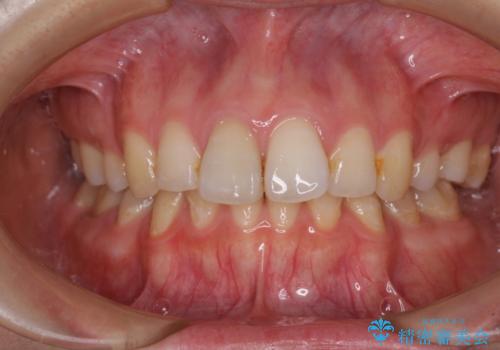

- 左下欠損部のインプラント治療と、右下の歯の痛みを気にして来院された患者様です。

左下の欠損部は、世界中で高い信頼を得ているストローマンインプラントを用いて治療を行うこととしました。

ただし、長期間欠損を放置していたことで、咬み合う上の奥歯が動いてしまっていたので、まずは上顎奥歯の部分矯正を行い、より理想的な咬み合わせを目指すこととしました。

まず生活歯髄療法を行い、その後部分矯正やインプラント処置を行いましたが、最初の処置から1年以上経っても右下奥の処置歯の神経組織に異常は認められませんでした。

部分矯正を行ったことで、違和感のない咬み合わせを達成することができました。